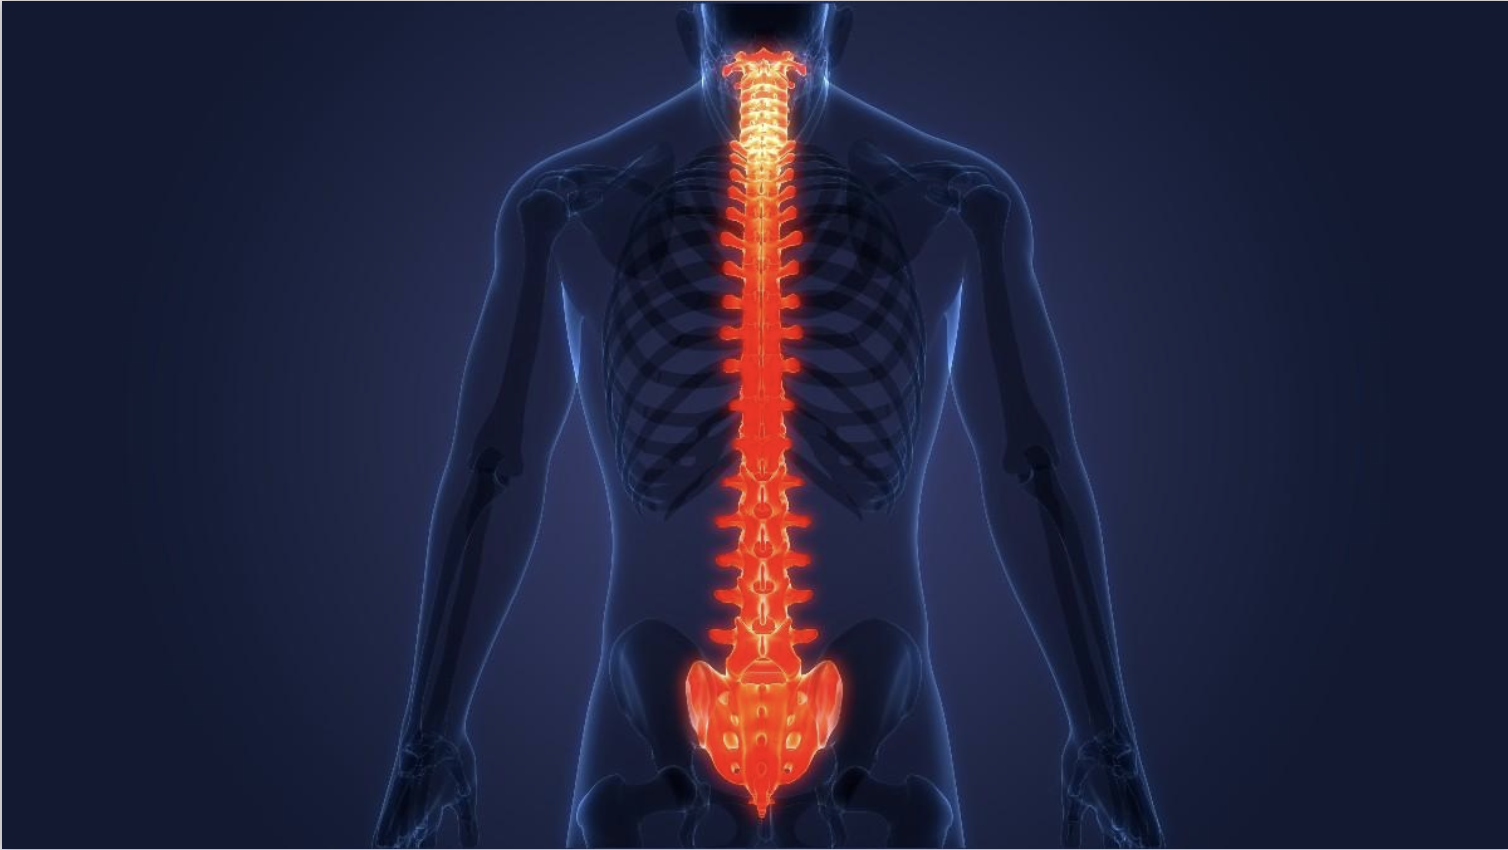

Enfermedades que tratamos

Enfermedades de columna

Diagnóstico y análisis integral de las enfermedades de columna vertebral y cerebrales

Hernia discal lumbar

Estenosis de canal lumbar

Hernia discal cervical

Estenosis de canal cervical

Mismos mecanismos que la estenosis lumbar pero en este segmento, la estrechez del canal, no comprime solo los nervios si no también la médula espinal. La compresión de la médula espinal puede general torpeza, rigidez, debilidad y dolor en los brazos y las piernas.

Listesis vertebral

Escoliosis degenerativa

Tumores del raquis vertebral

Las vértebras, nervios u estrictiras de la columna vertebral, como el resto de las estructuras del cuerpo humano, pueden desarrollar tumores. Estos tumores, dependiendo de localización y tamaño, puede ser extirpados mediante cirugía.

Infecciones vertebrales

Puede aparecer infecciones en los discos (discitis), en las vértebras (espondilitis) u otras estructuras de la columna vertebral. La mayoría de estas infecciones se tratan solamente con antibióticos, pero en ocasiones requieren de cirugía para evacuarlas o descomprimir estructuras.